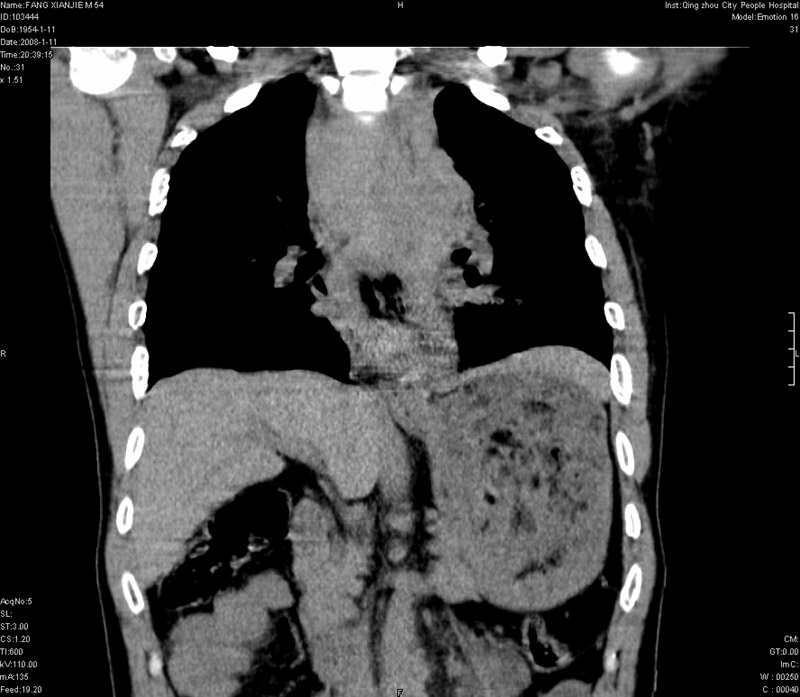

男性,40岁。胸部被车压伤伴胸痛1小时来院就诊。检查:一般情况尚可,血压110/80,胸部及上腹部压痛。结果在三天后公布。骨窗在横断位、冠矢状显示肋骨、胸椎、和胸骨未见骨折征象。

ct11308:胸部外伤1小时(证实病例) (2008-1-13 16:2)结果如下:病人入院后两小时后症状加重,8小时后在征得病人家属同意做了ct增强扫描。如下图。最终临床诊断:外伤性胸主动脉破裂并纵隔内血肿。由于有运动性伪影,胸骨在矢状面重建的图像似有骨折征,这是一种假象,我们称之为“假骨折”,这在多层ct重建中经常性遇到,必要时要结合横断图像鉴别之。现在,病人的一般情况较差,是否要手术家属尚有争议,如果手术修补,难度较大,需要专门预定制作固定支架。

以下是引用拾荒者在2008-1-16 18:46:00的发言:[br]ct11308:胸部外伤1小时(证实病例) (2008-1-13 16:2)结果如下:病人入院后两小时后症状加重,8小时后在征得病人家属同意做了ct增强扫描。如下图。最终临床诊断:外伤性胸主动脉破裂并纵隔内血肿。由于有运动性伪影,胸骨在矢状面重建的图像似有骨折征,这是一种假象,我们称之为“假骨折”,还有双侧肋骨的“假骨折”,这在多层ct重建中经常性遇到,必要时要结合横断图像鉴别之。现在,病人的一般情况较差,是否要手术家属尚有争议,如果手术修补,难度较大,需要专门预定制作固定支架。[br][br]再次表示感谢!

当然,对于该病例,其它非重要的诊断还有:右侧少量气胸;左侧胸腔积液;左侧轻度肺挫裂伤。对于纵隔内血肿,我们曾经遇到过多例,也有怀疑主动脉的破裂,但是,均未得到具体出血部位的明确诊断。